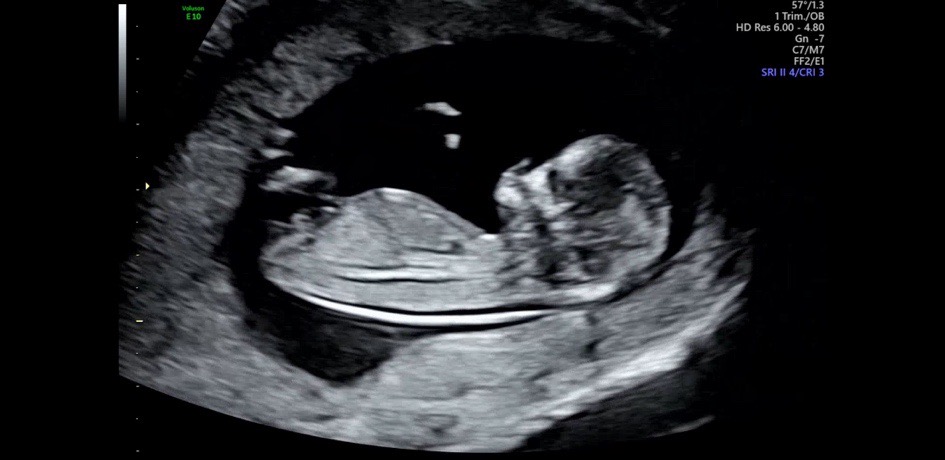

아들이네요~

각도법 봐주세용

각도법 보실줄 아실까용,,??